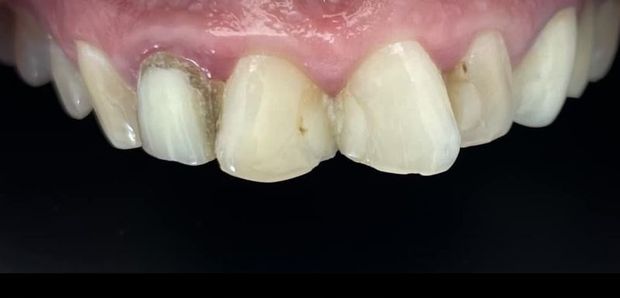

Licówki pełnoceramiczna wykonane cyfrowo w systemie CAD/CAM w przypadkach, kiedy poprawiamy estetykę – kształt i kolor zębów.